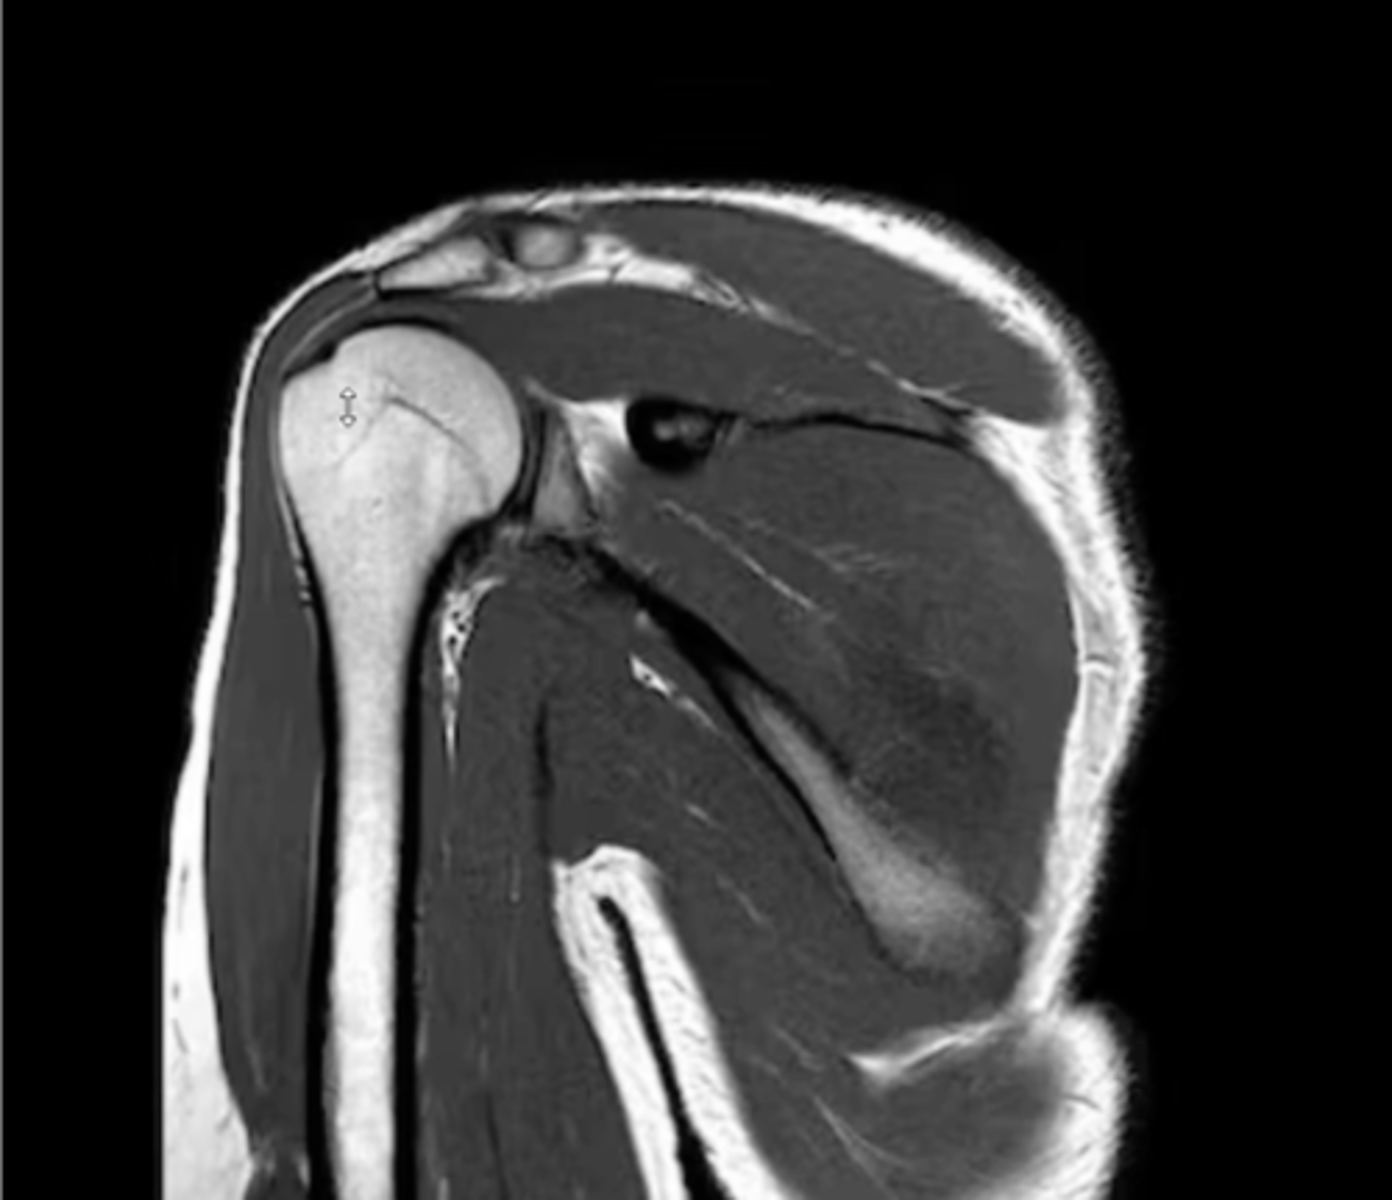

1. Sagittal = slices outside --> in

2. Coronal = slices w/ a traditional AP view

3. Axial = slices looking down

Explain the difference between each of the MRI slices.

Anterior coronal view of the shoulder -- key to setting this image up is finding the coracoid process, which is NOT present on the back side

What type of view is this? Anterior vs. posterior? How do you know?

AC joint, coracoid, short head of biceps (attaching to the coracoid), long head of biceps (making its way to attach to the superior glenoid labrum), anterior deltoid, and posterior deltoid

Which structures are present in this image as we work our way inwards towards the glenoid fossa and labrum?

1. Posterior coronal view

2. NO CORACOID

3. Posterior deltoid

1. What view is this image?

2. How do you know?

3. Which structure is being pointed to?

2. NO CORACOID -- spine of the scapula

3. Superior = spine of the scapula, inferior = infraspinatus

3. Which structures are being pointed to?

2. Glenoid

2. Which structure is being pointed to?

1. Anterior

2. Coracoid

1. Lateral deltoid

2. Acromion

3. Clavicle

4. Supraspinatus footprint

5. Glenoid

Working our way around clockwise, which structures are being pointed to?